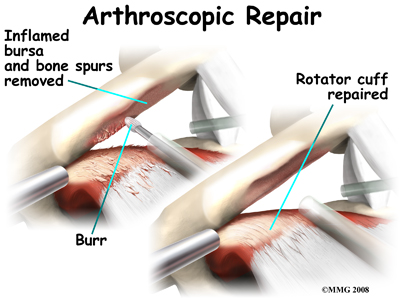

Subacromial Decompression

The goal of surgery is to increase the space between the acromion and the rotator cuff tendons. Taking pressure off the tissues under the acromion is called subacromial decompression. The surgeon must first remove any bone spurs under the acromion that are rubbing on the rotator cuff tendons and the bursa. Usually the surgeon also removes a small part of the acromion to give the tendons even more space. In patients who have a downward tilt of the acromion, more of the bone may need to be removed. Surgically cutting and shaping the acromion is called acromioplasty. It gives the surgeon another step to get pressure off (decompress) the tissues between the humerus and the acromion.

There are many small instruments that have been specially designed to perform surgery in the joint. Some of these instruments are used to remove torn and degenerative tissue. Some of these instruments nibble away bits of tissue and then vacuum them up from out of the joint. Others are designed to burr away bone tissue and vacuum it out of the joint. These instruments are used to remove any bone spurs that are rubbing on the tendons of the shoulder and smooth the under surface of the acromion and AC joint.